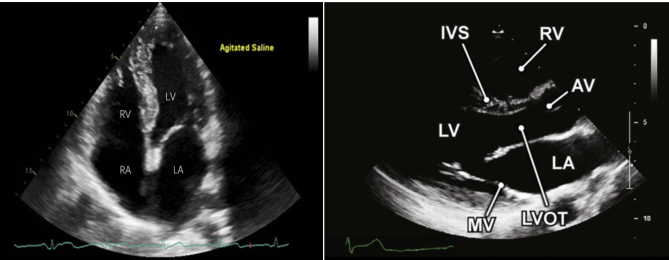

1.1  心脏各腔室形态观察、评估

首先,在剑突下四腔心切面(SC4C切面),观察心脏的整体情况,该切面主要优先评估有无心包积液和心脏压塞,然后根据目测评估各个心脏腔室的相对运动情况,是否出现明显的限制心包运动障碍的表现。相关特征图形如图1所示

在胸骨旁长轴(PLAX)切面,我们可以测量左心室、右心室舒张末前后内径和主动脉根部的内径及左心房内径。左心室等容舒张期进行测量,男性左心室心腔大小为4.2~5.9 cm,女性为3.9~5.3 cm。操作示意图见图3。

图片

图3. PLAX下测量左心室舒张末前后径(黄色)、右心室舒张末前后径(绿色)、左心房内径(红色)、主动脉根部内径(蓝色)的示意图